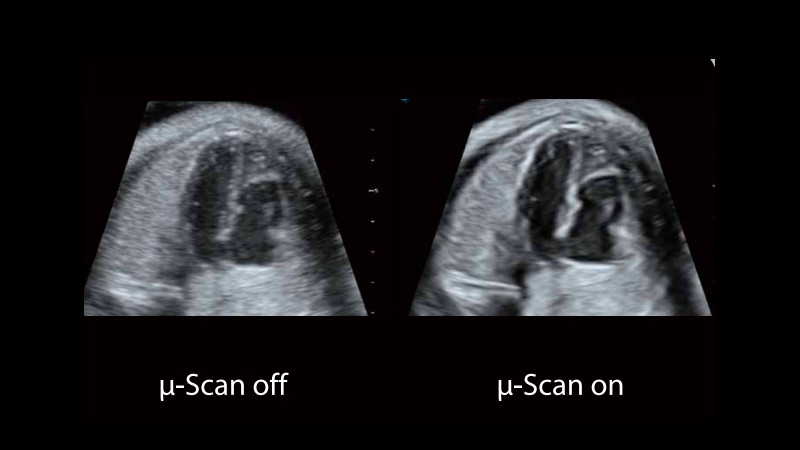

• μ-Scan+新一代微米成像技术

新一代微米成像技术大大提高了器官和病变的可见性。高清对比度分辨率将抑制斑点噪声,同时保持真实的组织结构。